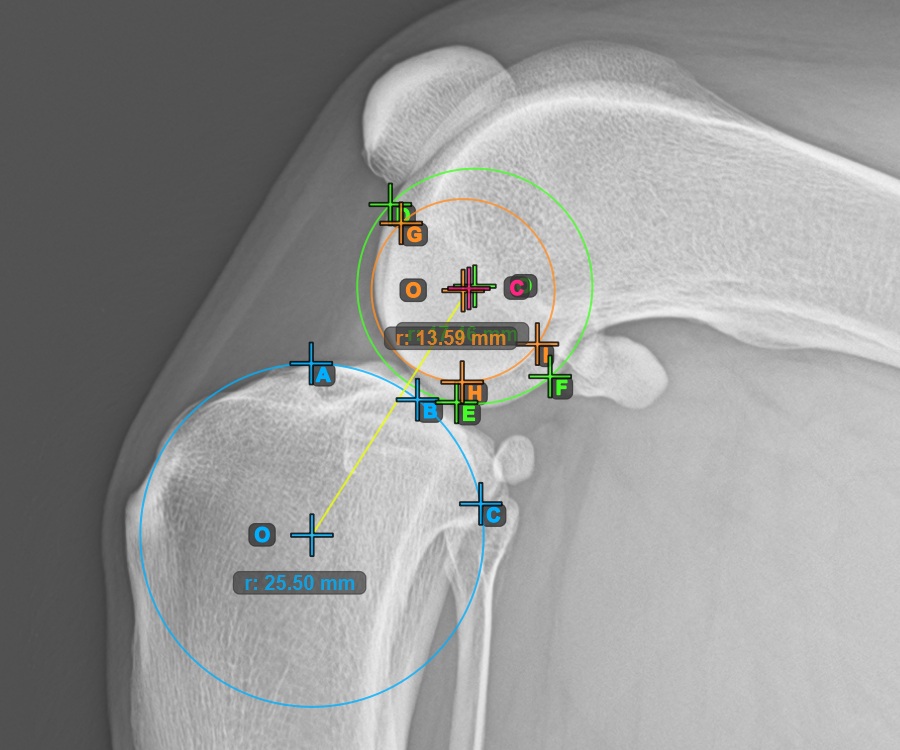

The image below represents a typical placement of the three points on the first Condylus Femoris.

![]()

Additionally, mark the three points on the articular surface of the second Condylus Femoris.